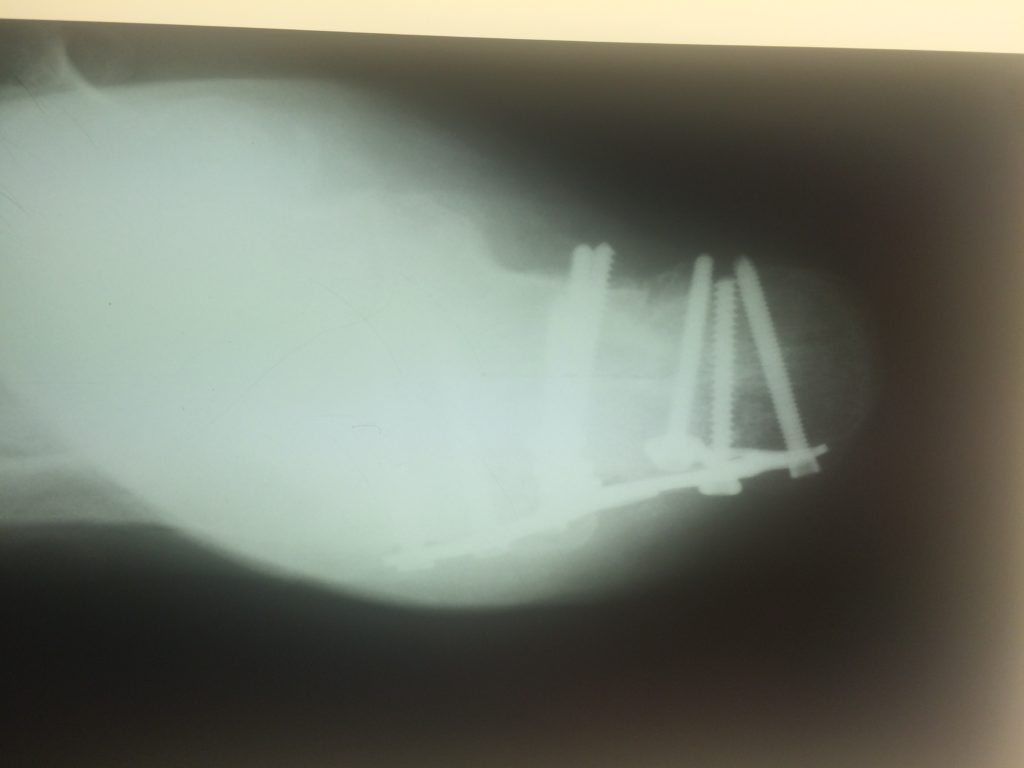

Применение материала Остеоматрикс при импрессионно-оскольчатом переломе пяточной кости

Операция – открытая репозиция, остеосинтез пяточной кости пластиной с костной ксенопластикой материалом «Остеоматрикс». На контрольных снимках в три месяца имеется консолидация перелома, миграции фиксатора нет, имеется остеоинтеграция ксенопластического материала.

Отдаленные результаты через 6 (шесть) месяцев: